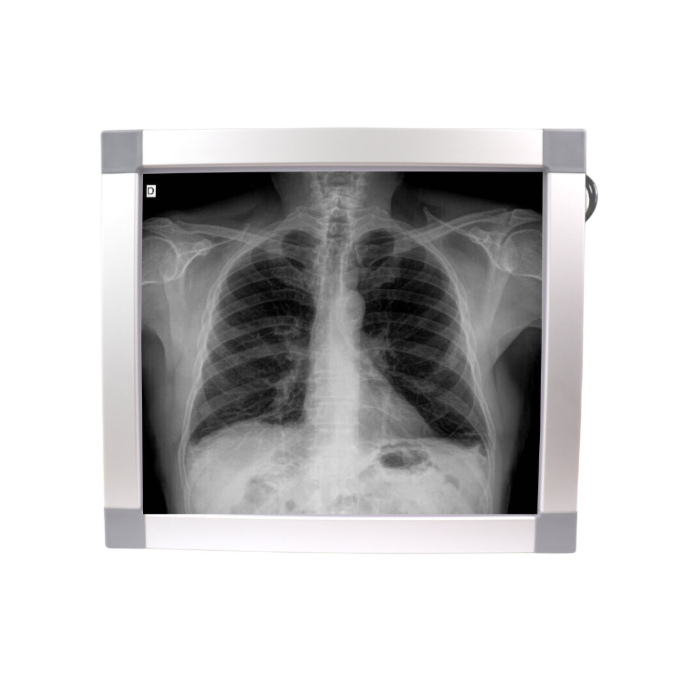

Negatoscopio 1 cuerpo, luz LED. KI

1 cuerpo. Estructura en aluminio. Iluminación Led